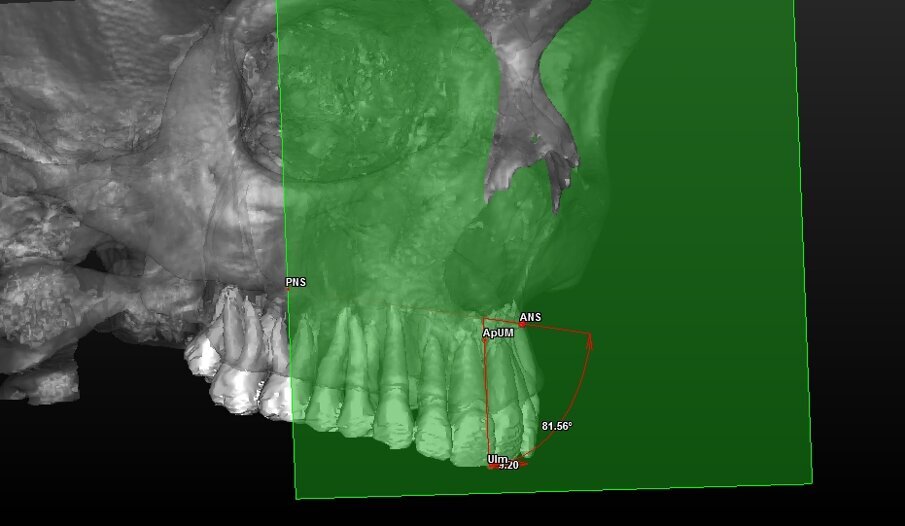

- 7 landmark per la valutazione scheletrica (Tab. 1) (Figg. 2, 3).

UIm: Punto mediano dei margini degli incisivi U11 e U21;Dai landmark dentali (U11, U21, ApU1R e ApU1L) sono stati ricavati due punti mediani calcolati direttamente dal software:

- ApUM: Punto mediano degli apici degli incisivi ApU1R e ApU1L.

Con questi è stato possibile tracciare una retta che passasse tra i punti UIm e ApUM e che possa essere considerato così il vero asse mediano degli incisivi centrali definendolo “Asse Incisale Superiore”.

Dai landmark ossei ANS e PNS è stata tracciata una retta passante per questi due punti definita “Asse Spinale”.

Componente dentale (Tab. 4) (Figg. 8, 9):

Fig. 8_Valutazione della componente dentale in visione para-frontale.

Fig. 9_Valutazione della componente dentale in visione di profilo.